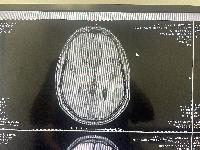

Another clear top view